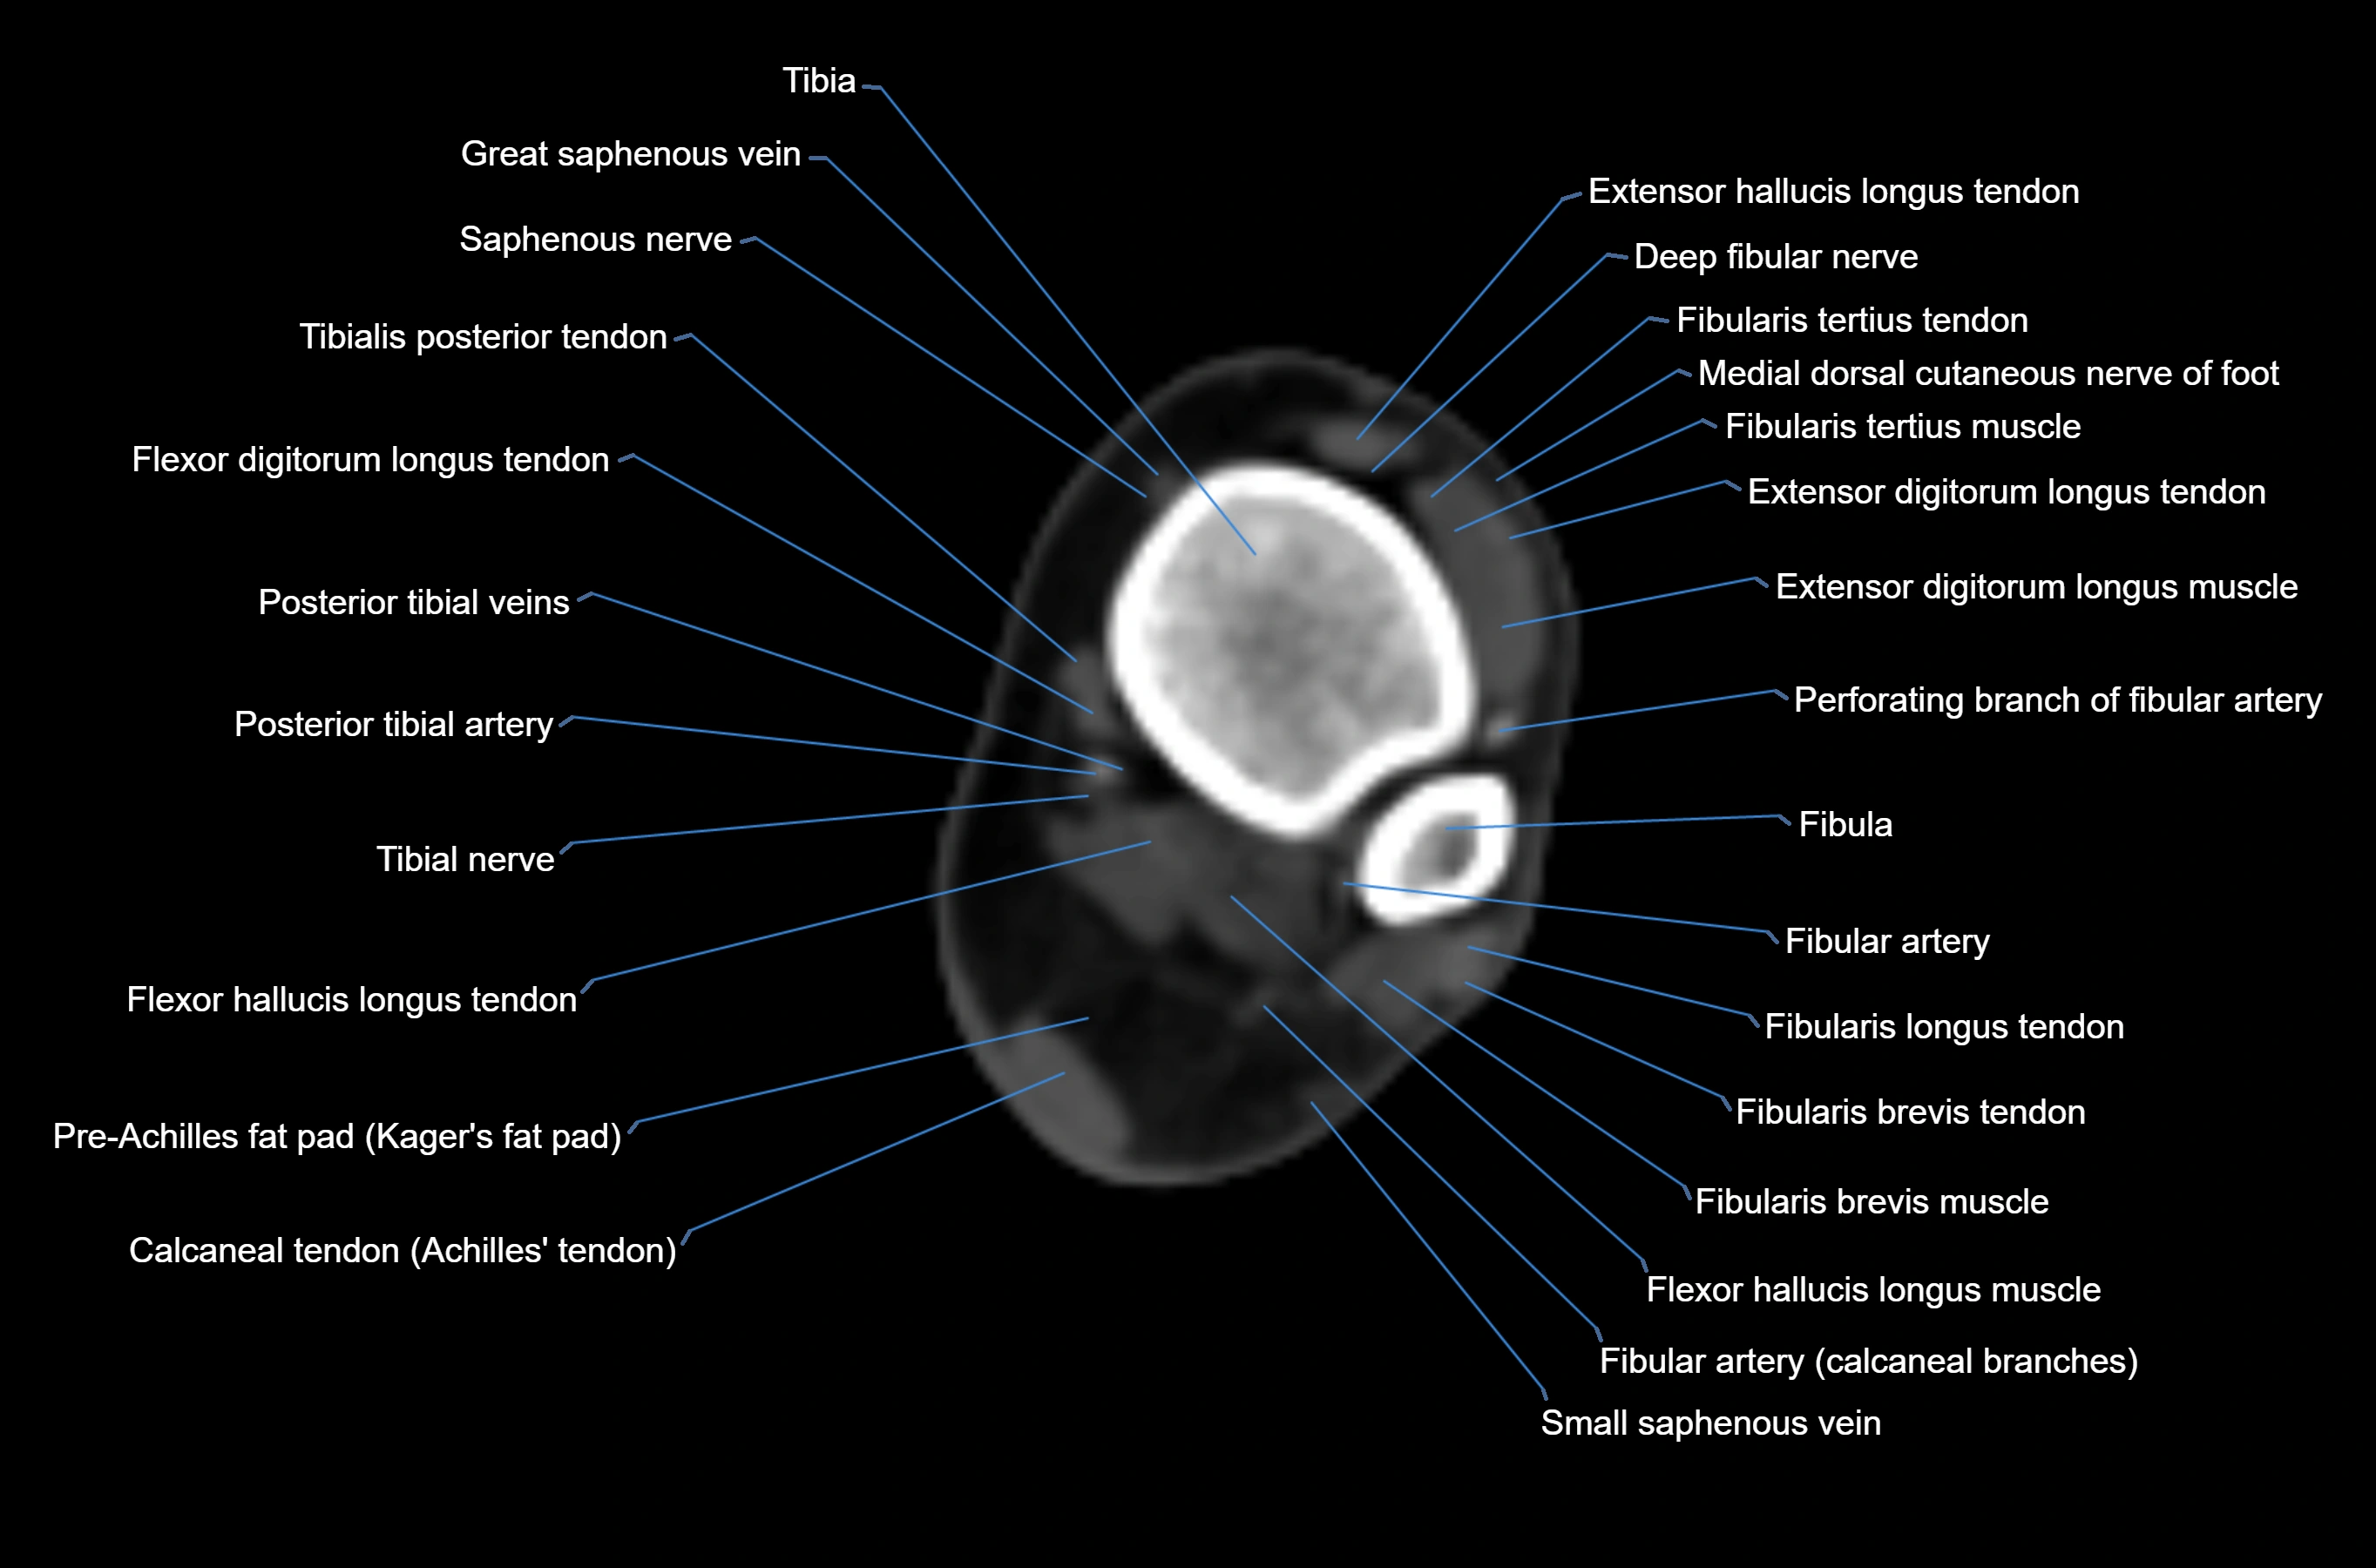

CT image